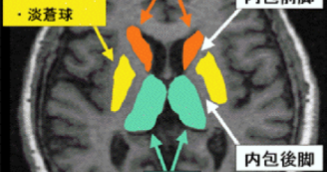

Ⅲa型:被殻から内包後脚に及ぶ血腫進展の被殻出血の症状と予後